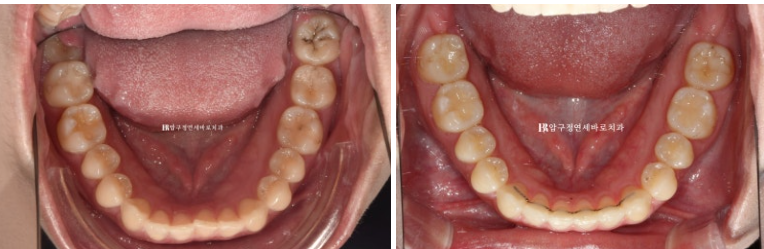

24.02~24.11

뒤로 쓰러져 있던 앞니가 나오면서 악궁모양이 네모진 형태에서 원형으로 바뀌었습니다.

아래 악궁모양이 좋아졌습니다.

중심선도 여전히 1mm 정도 차이가 나지만 처음에 비해 개선되었습니다.

옥니와 덧니가 해결이 되니 미소가 훨씬 깔끔하고 환해보입니다.